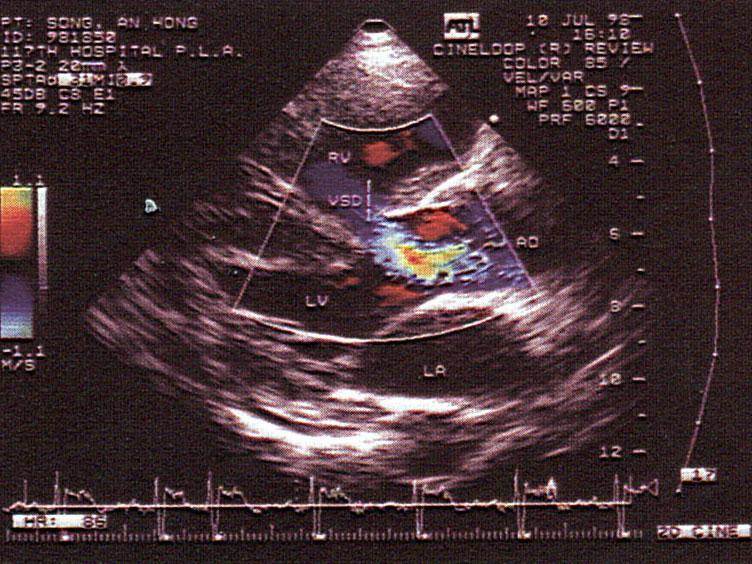

该切面未显示法洛四联症哪一症?(?)A.主动脉骑跨B.室间隔缺损C.肺动脉狭窄D.右室肥厚E.左心缩小

问题 该切面未显示法洛四联症哪一症?(?)

选项 A.主动脉骑跨 B.室间隔缺损 C.肺动脉狭窄 D.右室肥厚 E.左心缩小

答案 C